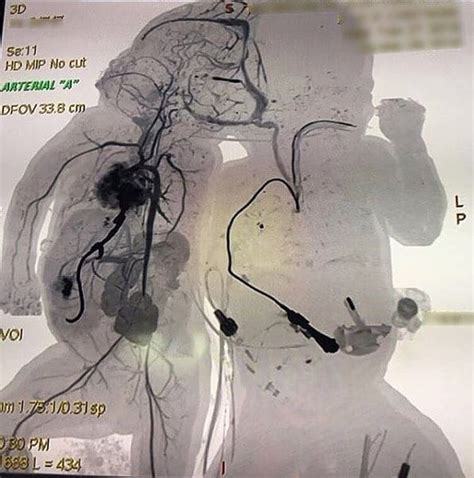

So, guys, not all conjoined twins are the same, right? The way they’re connected really varies, and this affects everything from their daily lives to potential medical interventions. Doctors have actually classified them based on where they are joined. The most common type is thoracopagus , where the twins are joined at the chest. They might share part of the sternum, abdomen, diaphragm, and sometimes even the heart. This is often the most challenging type for separation because of the shared vital organs, especially the heart. Then there are omphalopagus twins, who are joined at the abdomen, usually from the sternum down to the navel. They often share parts of the liver, intestines, and diaphragm, but their hearts are usually separate, which can make surgical separation more feasible than in thoracopagus cases. Another type is ischiopagus , where the twins are joined at the pelvis and share lower abdominal organs, rectum, and bladder. This type is often more difficult to separate due to the shared lower body structures and potential for significant functional impairment after separation. Less common types include pygopagus , joined at the back, and craniopagus , joined at the head. Craniopagus twins are particularly rare and present unique challenges because the head is such a sensitive area, often involving shared brain tissue or blood vessels, making separation extremely risky, if not impossible. The classification is super important because it guides the entire medical approach. Each type requires a tailored plan, considering the specific shared anatomy, potential risks, and the overall health of the twins. The medical team will meticulously map out the connections using advanced imaging techniques like MRI and CT scans to understand exactly what they’re dealing with. This detailed understanding is critical for planning any potential separation surgery, which is a massive undertaking. The decision to attempt separation is never taken lightly and involves extensive ethical considerations, weighing the potential benefits against the risks. Sometimes, separation isn’t medically possible or advisable, and the focus then shifts to ensuring the twins have the best possible quality of life together, with support for any associated health issues.